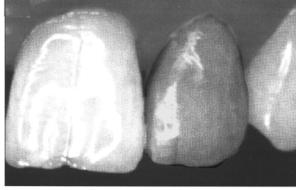

При переломе коронки с обнажением пульпы во время обследования визуально или при зондировании выявляется пульпа ярко-красного цвета, резко болезненная, зуб реагирует на температурные раздражители (рис. 18).

Рис. 18: Горизонтальный перелом коронки зуба

Лечение травматического пульпита зависит от срока обращения пациента к врачу. Если это происходит в первые 12 часов после травмы и нет инфицирования, проводится биологический метод лечения пульпита прямым покрытием пульпы лечебными пастами и защитной коронкой на длительный срок до тех пор, пока электровозбудимость пульпы будет определяться нормальной в течение года. После этого защитную коронку снимают, восстанавливают анатомическую форму зуба по показаниям.